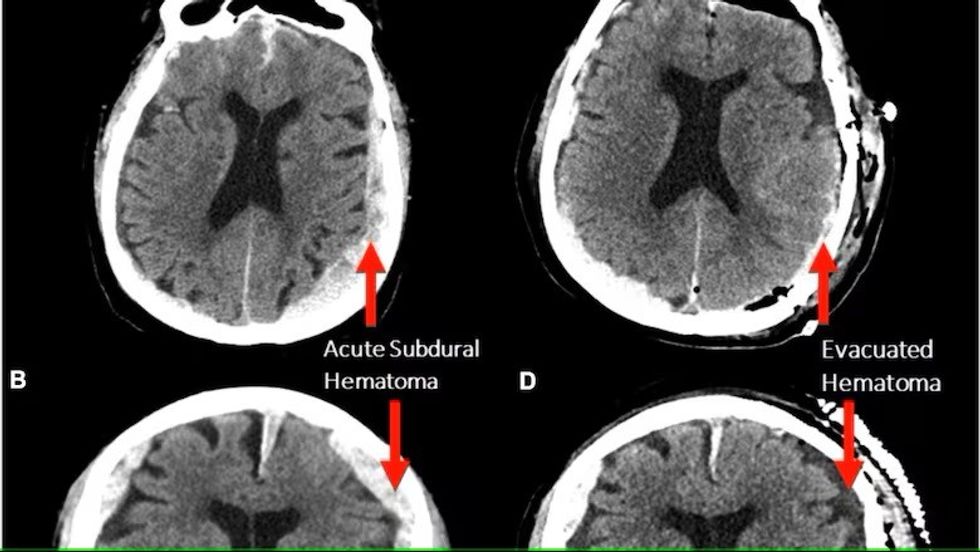

Gjatë njërit prej skanimeve, pacienti papritur pësoi një atak kardiak dhe ndërroi jetë, gjë që u mundësoi mjekëve dhe studiuesve të regjistronin për herë të parë aktivitetin e trurit para, gjatë dhe menjëherë pas vdekjes.